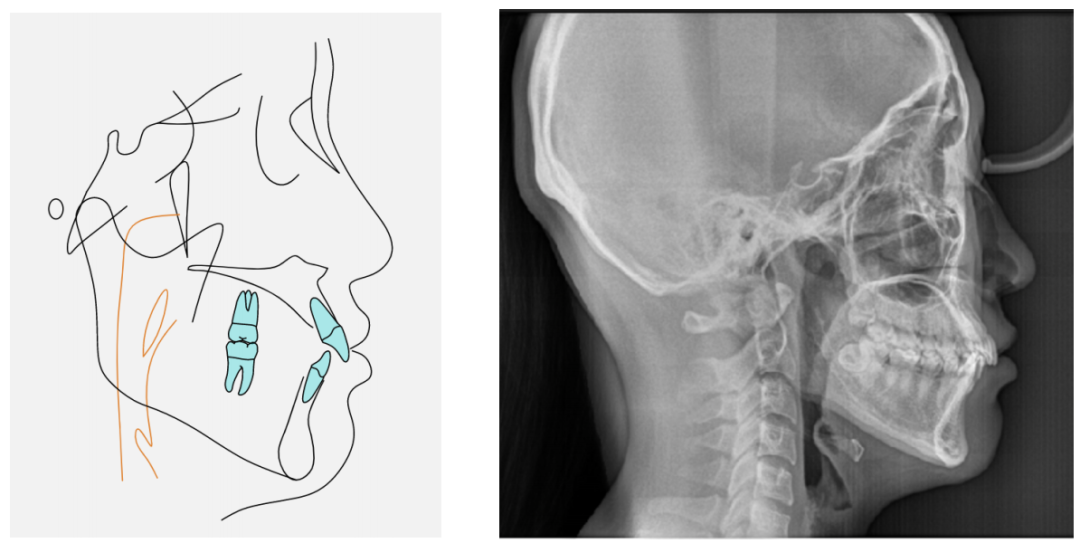

从面部基本特征看:软组织侧貌微前突,颏部形态良好。

如图1-3⼝内情况所示:上下前牙轻度拥挤、上前牙唇倾、牙弓形态尚可。

如图1-4曲断片所示:28、38阻⽣,未见牙根吸收,牙周状况良好。左侧髁突见吸收。

图1-7头影测量数据